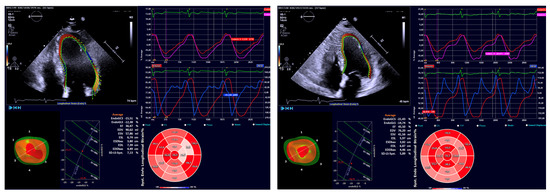

4.2. Echocardiographic Protocol